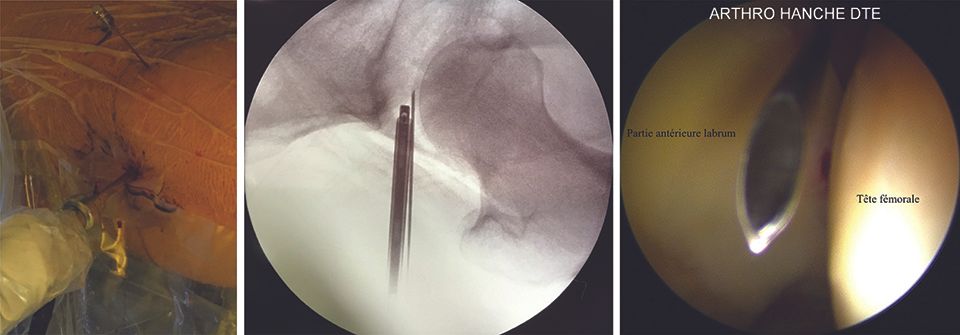

The entry point in the skin is made where the line passing over apex of the greater trochanter (perpendicular to the ASIS–patella line) intersects with the line mapping the anterior edge of the femur. This point is situated approximately 1 cm above and 1 cm in front of the greater trochanter (Fig. 3, left). Using the image intensifier, if the patella is facing up, the needle will be parallel to the floor and pointed towards the clear space in the separated joint (Fig. 3, right).

This technique, coupled with general anaesthesia and a neuromuscular blocker to aid the relaxation of the anterior iliofemoral ligament, allows a reduction in traction force (joint separation) from 500 N to 230–300 N (38,39), thus reducing the risks of potential complications (see “Complications”, above). Next, the nitinol guide is inserted into the spinal needle (Fig. 4). After withdrawing the spinal needle, the hollow trocar is introduced on the nitinol guide (Fig. 5) and the arthroscope is inserted. The arthroscopic view is shown in Figure 6.

The entry point in the skin is situated beside the intersection of the ASIS–patella line and the perpendicular line that passes over the apex of the greater trochanter, either over or slightly distal to it (Fig. 7, left). The needle is inserted obliquely, approximately 45° superiorly and 30° posteriorly, guided at first by the image intensifier (Fig. 7, centre) and subsequently by the arthroscope, to arrive in the triangular zone formed by the labrum and the femoral head (Fig. 7, right).